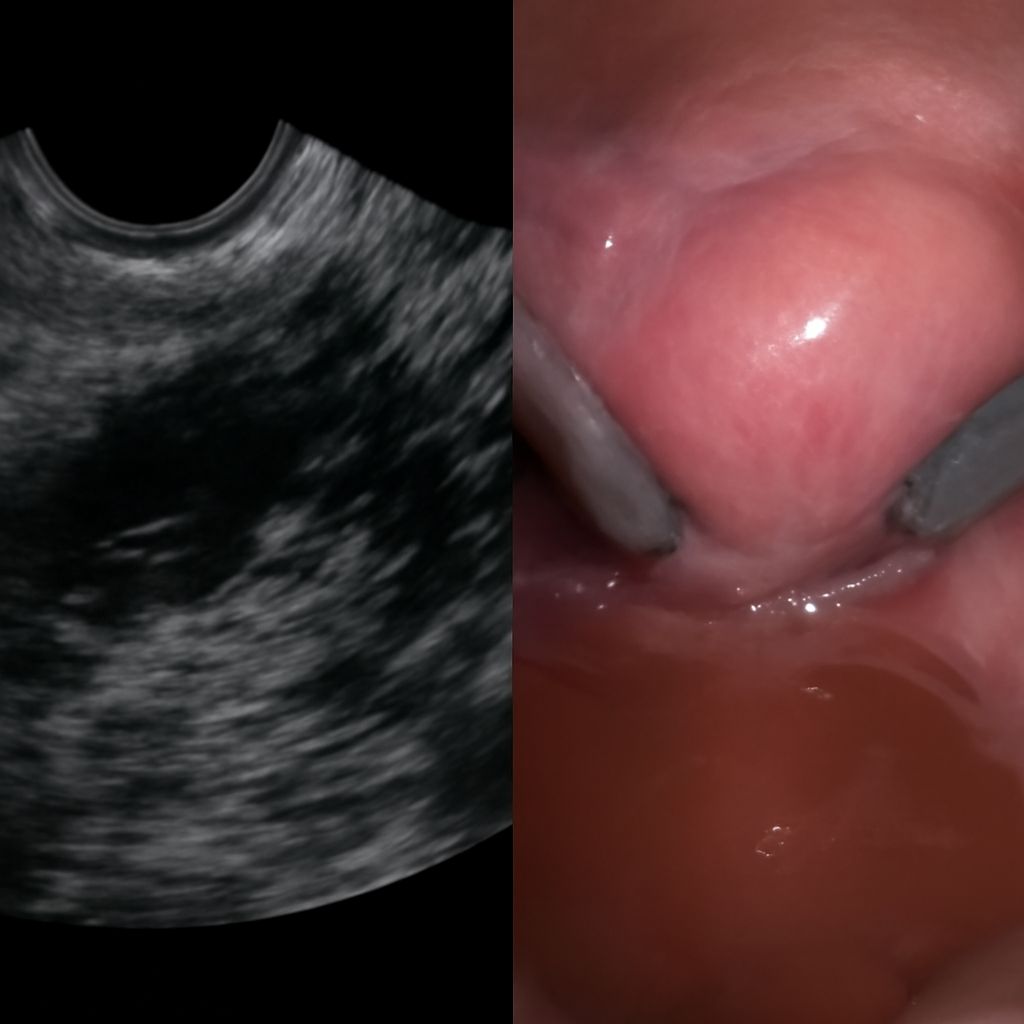

Transvaginal ultrasound involves a thin, covered probe inserted a few centimeters into the vaginal canal. Patients insert the probe themselves or the sonographer does so with your guidance. The procedure feels similar to a gynecological speculum exam and is typically better tolerated than patients expect. Images taken transvaginally show significantly more detail than transabdominal images for most pelvic structures because the probe sits closer to the target anatomy.

When the primary focus is the ovaries, the sonographer measures each ovary and documents the size, shape, and any follicles or cysts present. An ovarian ultrasound identifies simple cysts, complex masses, polycystic ovary morphology, and free fluid around the ovaries that could indicate rupture or torsion. Doppler flow assessment is often added to evaluate blood supply to ovarian masses, which helps differentiate benign from potentially concerning lesions.

Ovarian imaging looks different than thyroid imaging despite both relying on ultrasound technology. While thyroid ultrasound images show nodule echogenicity, calcifications, and vascularity in a superficial gland, ovarian imaging involves deeper structures where image quality depends heavily on bladder fullness and body habitus. The principles of ultrasound interpretation are the same, but the anatomy and clinical questions are entirely different.